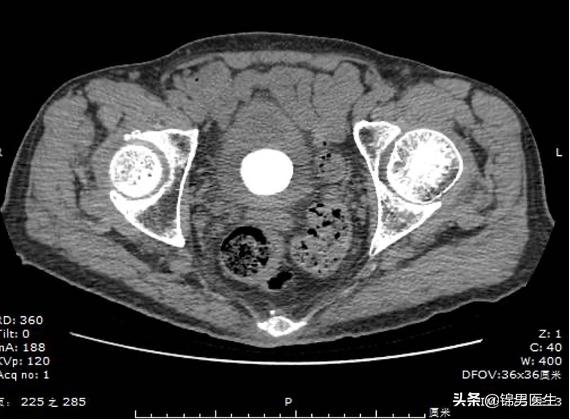

次日,再次行泌尿系CT检查,结果提示:肝、左肾多发囊肿;考虑膀胱结石;腹主动脉及其分支管壁多发钙化。

鉴于患者年龄偏大,再加上患有前列腺增生等疾病,综合各种因素,建议进行手术治疗。进行全身麻醉生效后,取膀胱截石位,常规络合碘消毒阴部及周围手术野,铺无菌巾、孔巾。应用丁卡因凝胶行局部浸润麻醉,电视监视下应用STORZ#22F膀胱镜,顺利置入,见膀胱内充满结石,大小不等,大者约4cm x4cm x4cm。顺序观察膀胱各壁及三角区,膀胱粘膜明显充血水肿,未见明显占位病变,双侧输尿管开口观察不清,用钬激光将结石击碎,部分随水冲出,部分取出,彻底冲洗,可见已碎细小结石可待以后自行排出,留置F20#o1ey尿管,水囊注水10m1。